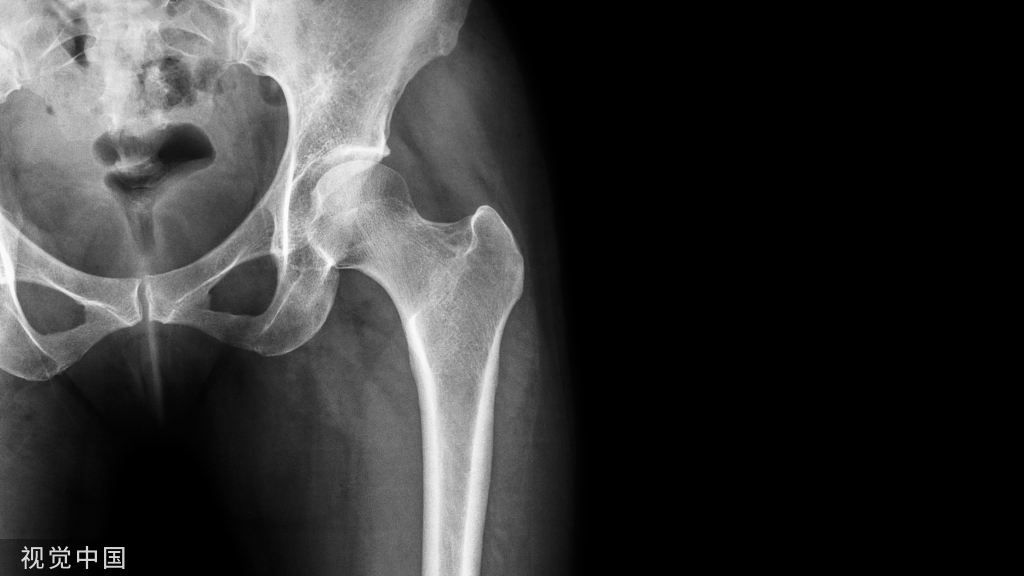

正确的下肢力线

下肢力线:三关节中心

假体置换后正确力线:经膝关节  均匀的应力分布平衡的韧带张力降低磨损

膝关节的机械轴线和解剖轴线髋、膝关节内、外翻时会影响力线

标准的骨性对线股骨的解剖轴——应力轴=5~7°胫骨的解剖轴——应力轴=0 °

假体对线股骨远端切骨垂直于力学轴线胫骨切骨垂直于胫骨力学轴线